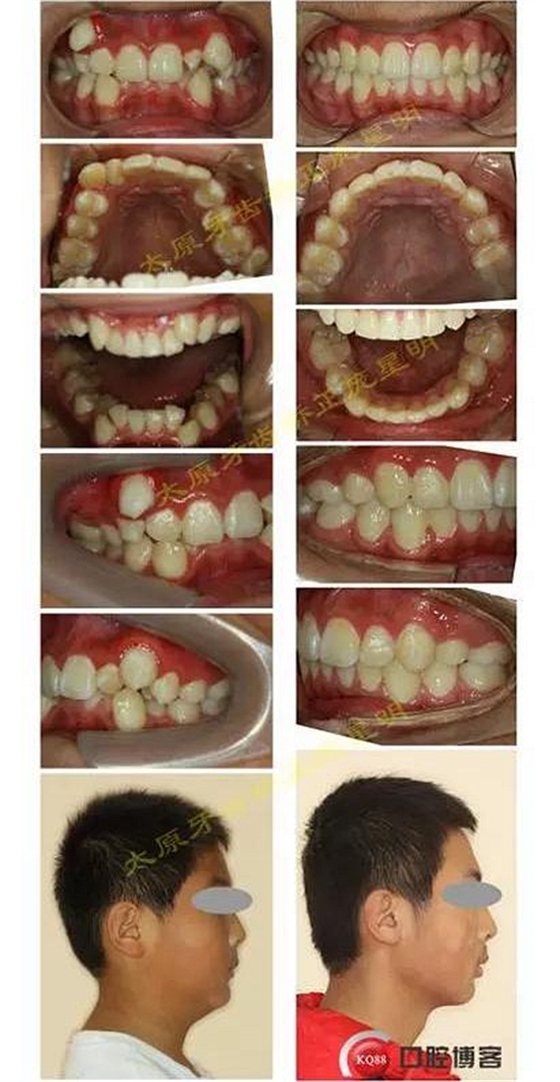

1500865770_445373.jpg1500865976_358577.jpg

此病例主要考慮的是擁擠度,磨牙及尖牙關(guān)系,前牙覆合覆蓋,生長(zhǎng)潛力和智齒。